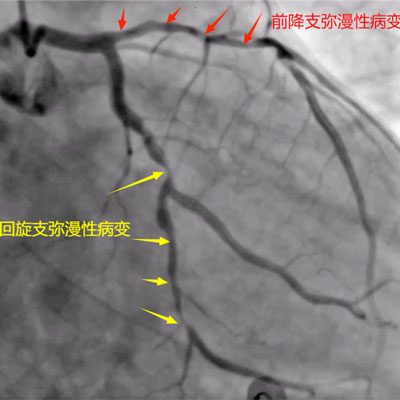

据了解,患者姓钟,男性,58岁,长期抽烟,4月20日因活动后胸痛2天于李家河卫生院就诊,完善相关辅检后考虑心肌梗死,由120送入最近胸痛中心——来凤县人民医院。来凤县人民医院胸痛中心按胸痛救治流程收治入院,入院后行冠脉造影提示:三支病变,前降支弥漫性病变,开口狭窄最重约40%,近段狭窄最重约90%,中段狭窄最重约80%,远段狭窄最重约50%,第一对角支开口至近段弥漫性病变,狭窄最重约80%;回旋支开口正常,于钝缘支分又前狭窄最重约90%,远段弥漫性病变,狭窄最重约80%;右冠开口正常,中段狭窄最重约50%。

获得家属同意后,考虑到患者病变复杂,来凤县人民医院心血管内科介入团队为患者制定了详细手术方案,因病变特殊性左冠前降支及回旋支两支血管需同期处理,导致手术更复杂,对术者要求更高。术中前降支使用球囊封堵法保护住了成角很大的对角支,回旋支扭曲使用双导丝技术成功植入支架,经过2小时努力同期完美处理前降支及回旋支病变结束手术。